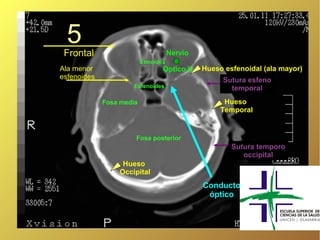

5

Frontal                             Nervio

Etmoides

Ala menor                        Óptico II    Hueso esfenoidal (ala mayor)

esfenoides                                         Sutura esfeno

Esfenoides                     temporal

Fosa media                             Hueso

Temporal

Fosa posterior

Sutura temporo

occipital

Hueso

Conducto

óptico

5 Frontal Nervio Etmoides Ala menor Óptico II Hueso esfenoidal (ala mayor) esfenoides Sutura esfeno Esfenoides temporal Fosa media Hueso Temporal Fosa posterior Sutura temporo occipital Hueso Occipital Conducto óptico